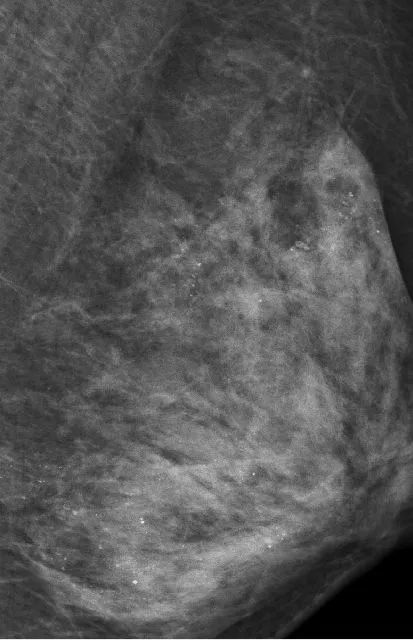

最让医生意外的是她的左侧乳房。乳腺X线检查时,发现里面全部都是细小如沙子一样的钙化灶,布满整个乳腺。

在X光片下,朱女士的乳腺里满是星星点点的钙化灶